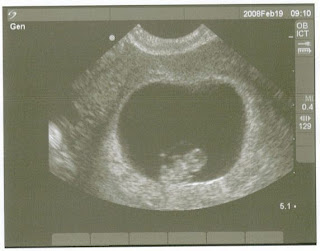

Baby Keenan's first photo shoot at nine weeks! Already has Daddy's big brain, ha ha!!

Well I am new at this blogging thing so I'm sure this page will get better with time! As I am sure you know by now Michael and I are expecting our first baby and couldn't be more excited! I thought this was a great way to keep our families connected with us throughout this magical journey. BabyKeenan is due on Septemeber 23 which makes me 10 weeks right now. We are praying everything continues to go as smooth as it has so far. We have seen BabyKeenan three times now, and it is overwhlemingly exciting everytime we see the baby. Michael was away for training last week when I had an ultrasound to see the baby and the heartbeat. I was sad he couldn't be there so my amazing midwife scheduled another ultrasound so Michael could see the baby and it's amazing heartbeat. So today we saw the baby and the heart was beating 171 beats per minute and babykeenan was wiggly, moving all around. I have a feeling this is going to be a busy baby, but then again he has a Daddy that can't sit still for more than two seconds. With every week that goes by the thought having a baby becomes more real and more exciting. I have a slight baby bump but not showing too much yet. I hope everyone enjoys this blog and I will do my best to keep you updated weekly on our progress. Michael and I are overjoyed to share this with our loved ones. So it begins.........!!!